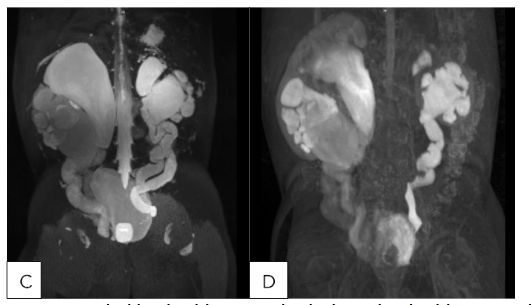

Representative MRU in Pediatric Patients with High-Grade Hydronephrosis

(A,B) 24 month old male with SFU Grade 4 hydronephrosis with UPJ morphology without obstruction/decompensation and (C,D) 23 month old female with bilateral duplex collecting systems with persistent grade 4 hydronephrosis following surgical reconstruction. (A) T2 MIP: Right kidney SFU grade 4, Left kidney SFU grade 1. (B) T1 Gd-enhanced MIP: Renal transit time is 2 minutes 1 seconds on the left, which is normal. Renal transit time is 1 minutes 47 seconds on the right, which is normal. (C): T2 MIP: Duplicated left kidney with cystic dysplasia of the upper left moiety and SFU grade 4 of the lower left moiety, Duplicated right kidney with SFU grade 4 of both upper and lower moieties, Tortuous ureters. (D) T1 Gd-enhanced MIP: Unit Patlak differential renal function is 56.9% on the lower left moiety and 43.1% on the upper left moiety. Renal transit time is 3 minutes 45 seconds on the left lower pole, which is nonobstructive. The left upper pole demonstrates trace contrast excretion. The equivocal range of the renal transit time of the right upper and lower pole is most likely related to capacious system. It does not appear to be high-grade obstruction.